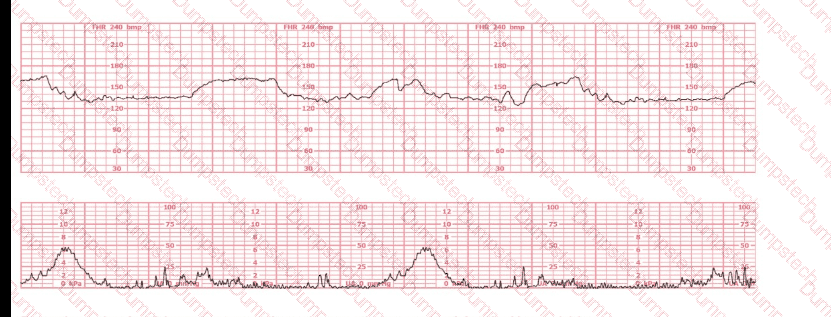

Based on the fetal heart rate tracing shown, the expected fetal pH would be:

(Full question)